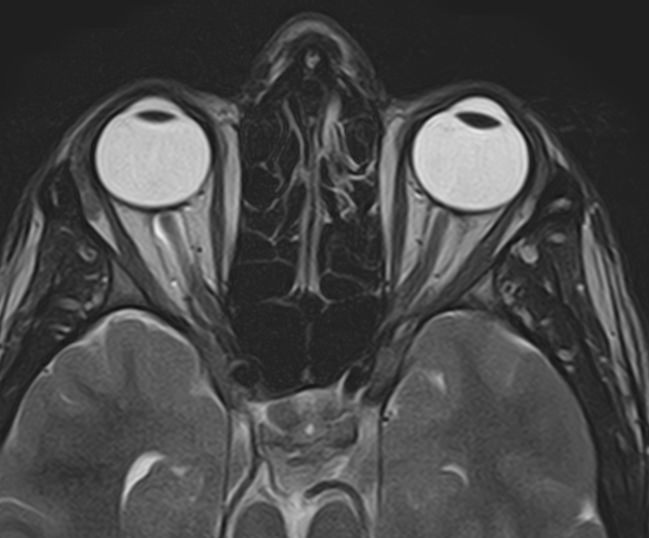

МРТ глазных орбит является современным способом диагностики патологии глазниц, в которых расположены глазные яблоки и их придатки (окружающая жировая клетчатка, зрительные нервы, слезные железы, мышцы глаза, связочный аппарат, кровеносные сосуды). МРТ орбит также позволяет получить детальную информацию о состоянии мягких тканей периорбитальных областей (тканей, окружающих глазницу).

Магнитно-резонансную томографию назначают при необходимости детального изучения мягкотканных структур глазниц. В результате исследования получают срезы анатомической области, на которых можно рассмотреть мельчайшие элементы. МРТ орбит обеспечивает визуализацию следующих структур:

• элементы глазного яблока, включая оболочки;

• периорбитальная клетчатка;

• мышечный аппарат;

• зрительный нерв;

• слезные железы.

Ангиорежим позволяет изучить сосуды глаза (глазная артерия и вены сетчатки).